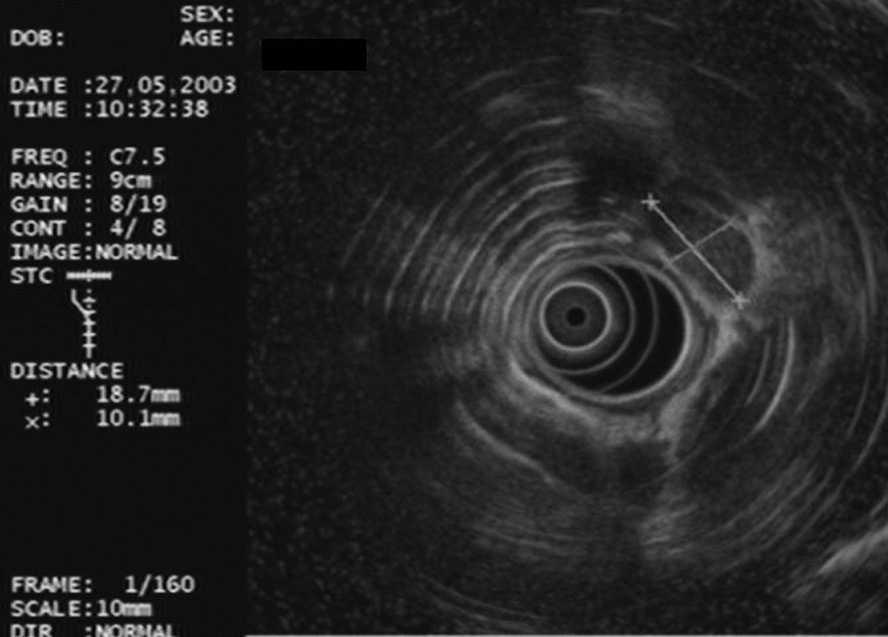

Durante la realización de la USE-PAAF, un citólogo se hallaba presente en la sala de exploración para valorar de forma inmediata la muestra obtenida. Parte de ésta se extendió sobre una laminilla y se tiñó con una tinción rápida (Diff-Quick®, Diagnostic Grifols S.A., España), mientras que el resto del material se conservó en alcohol para su posterior tinción con Papanicolau y en solución salina para procesarla en forma de bloque celular (fig. 4). Se consideró que una lesión era neoplásica cuando se identificaron células malignas, mientras que la ausencia de células malignas junto con la presencia de linfocitos normales se consideró diagnóstica de adenopatía benigna. Para el diagnóstico de tuberculosis se estimó necesaria la identificación de granulomas caseificantes y/o cultivo de Löwenstein positivo. Para el análisis estadístico se consideró positivo cualquier resultado diferente de adenopatía benigna.

Fig. 4. Metástasis de adenocarcinoma.